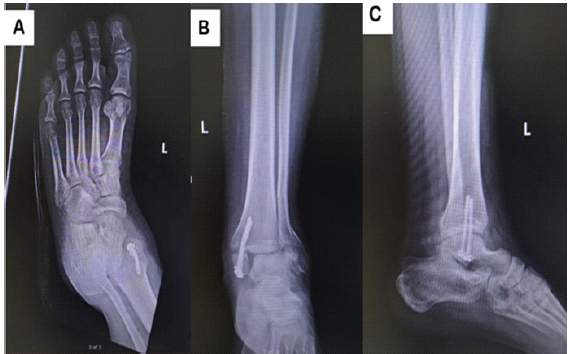

A 25-year-old male with a history of left medial malleolar fracture, previously fixed with two screws in February 2025, presented to the Emergency Department 5 months later following a motorcycle accident that resulted in a new bimalleolar fracture of the left ankle. On examination, there was moderate swelling and a limited range of motion (ROM) of the left ankle. Distal neurovascular status was intact, and all compartments were soft. A superficial abrasion was noted over the medial aspect of the left foot. An X-ray of the left ankle revealed a bimalleolar fracture along with non-union of the medial malleolar fracture (Fig. 1).

Figure 1: Pre-operative anteroposterior (a and b) and lateral (c) X-rays of the left ankle showing a bimalleolar fracture and bent medial malleolar screws with fracture non-union from previous fixation.